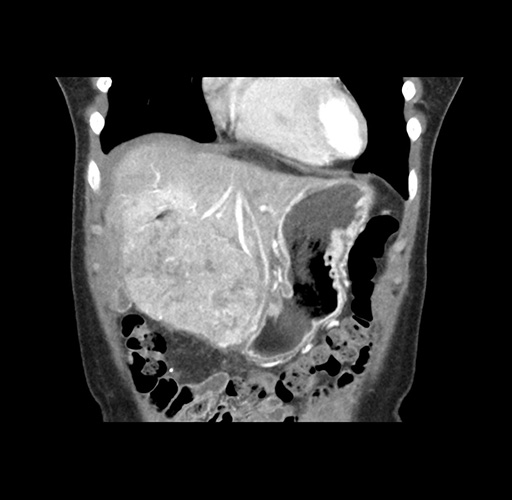

Imaging Analysis

Look through the patient's CT scan to identify any areas of concern for the necessary procedure.

Based on your CT findings, which issue(s) would give reason for "planned slowing down moment(s)" in this case?

Considering a standard left lateral sectionectomy procedure, what step(s) of the operation would you do differently in this case ?